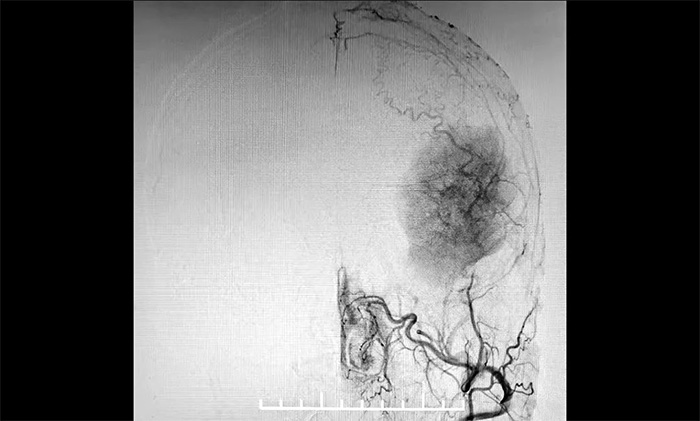

發(fā)生于額顳部位的巨大腦膜瘤,治療方法主要為顯微外科手術(shù)切除。該腫瘤不僅體積巨大,橫跨多個(gè)重要腦功能區(qū),行DSA檢查發(fā)現(xiàn),腫瘤包裹纏繞多根重要的動(dòng)脈血管,血供十分豐富。若直接行手術(shù)切除腫瘤,容易因術(shù)中大出血而危及患者生命。

▲ DSA檢查示:腫瘤血供豐富

4A病區(qū)醫(yī)生團(tuán)隊(duì)與患者和家屬充分溝通,明確手術(shù)方案的必要性和風(fēng)險(xiǎn)性,并獲得充分理解、簽字同意后,11月23日,醫(yī)院學(xué)術(shù)副院長(zhǎng)兼神經(jīng)內(nèi)科4A病區(qū)主任席剛明教授在4A病區(qū)副主任王貴平博士及介入團(tuán)隊(duì)協(xié)助下,首先為患者在全麻下行腦血管造影+腦膜瘤栓塞手術(shù)。手術(shù)過(guò)程順利,復(fù)查腫瘤供血血管基本不顯影,為下一步進(jìn)行腫瘤切除創(chuàng)造了有利條件。